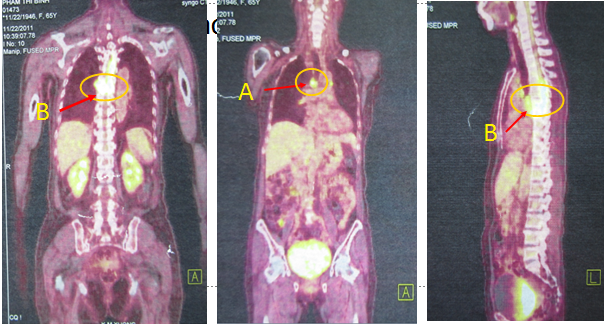

Vì vậy bệnh nhân được chỉ định chụp PET/CT để tìm vị trị tổn thương của ung thư nguyên phát. Kết quả chụp PET/CT không phát hiện thêm vùng tổn thương nào khác và không tìm được ổ ung thư nguyên phát. Cụ thể: chỉ thấy  hình ảnh hạch trung thất tăng hấp thu FDG với SUV max là 5,61, hình ảnh tiêu xương và phá hủy thân đốt sống có chèn ép tủy tại mức D2 -D7tăng hấp thu FDG mạnh với SUV= 11.04, dịch màng phổi phải tăng hấp thu FDG nhẹ.

(Trên hình ảnh PET/CT toàn thân: (A): hạch trung thất; (B): Tổn thương đốt sống có chèn ép tủy sống)